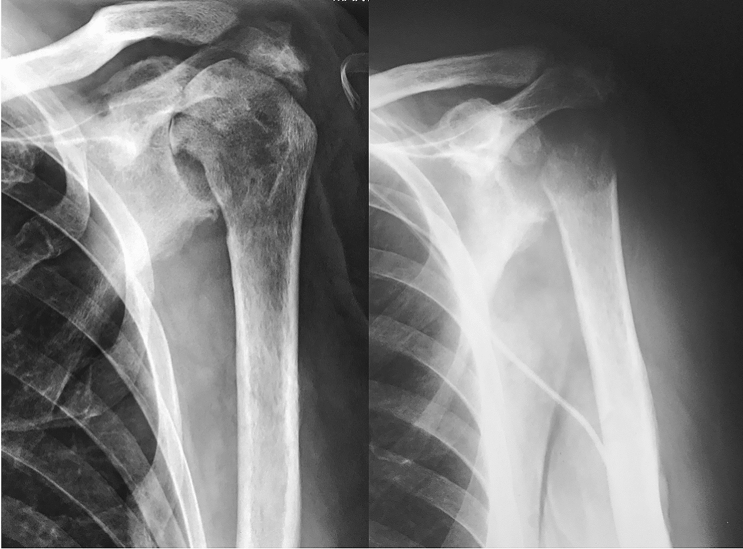

In recent years, the rapid development on shoulder arthroplasty components led to an exponential increase in the use of total prostheses and especially of reverse shoulder arthroplasties (RSA) [48–50]. Although the overall success rate is high [51, 52], the number of failures has proportionally increased. The main cause for revision is instability, followed by peri-prosthetic infection, aseptic loosening of components and fractures [53]. Currently, the incidence of infection after SA reach up to 2.9% for primary SA and up to 15.4% for revision arthroplasty [54] with devastating consequences. There are several options for the treatment of failed shoulder arthroplasty, including antibiotics, arthroscopic debridement, open debridement with and without preservation of components, one stage revision and two staged revision with or without a spacer. However, revision surgery for recalcitrant infected arthroplasty or persistent component loosening is challenging and the options are limited due to the loss of bone stock and soft tissue tension [7]. In many of these cases where preservation of prosthetic components carries a high failure risk or even jeopardize patient’s life due to disseminated sepsis, SRA stands as an option for infection eradication [6, 55] (Fig. 3).

Fig. 3.

Case 3: 52-year-old male diagnosed with schizotypal disorder presented after a seizure with a glenohumeral fracture-dislocation. a Left: anteroposterior radiograph of left shoulder showing fracture-dislocation of proximal humerus. a Right: He was initially treated by plate osteosynthesis. b Left: some weeks later underwent revision surgery, with hardware removal and hemiarthroplasty. In the immediate postoperative period, he began with general sepsis signs and purulent wound effusion. b Right: SRA was performed due to failure to solve periprosthetic infection after two surgical revisions, worsening of the patient’s general condition, low functional demand of the patient and being the non-dominant arm. c At 24 months mark, the patient was free of infection, had complete pain relief and was satisfied with the functional outcome to develop activities of daily life

Fig. 4.

Case 4: a 75 year-old female patient presented with hematogenous osteomyelitis of the left shoulder. Left: anteroposterior radiograph shows osteolysis and cystic lesions of the humeral head. Right: after 6 months of non-responsiveness to antibiotics and four surgical procedures for debridement and thorough irrigation, a SRA was performed to resolve the infection